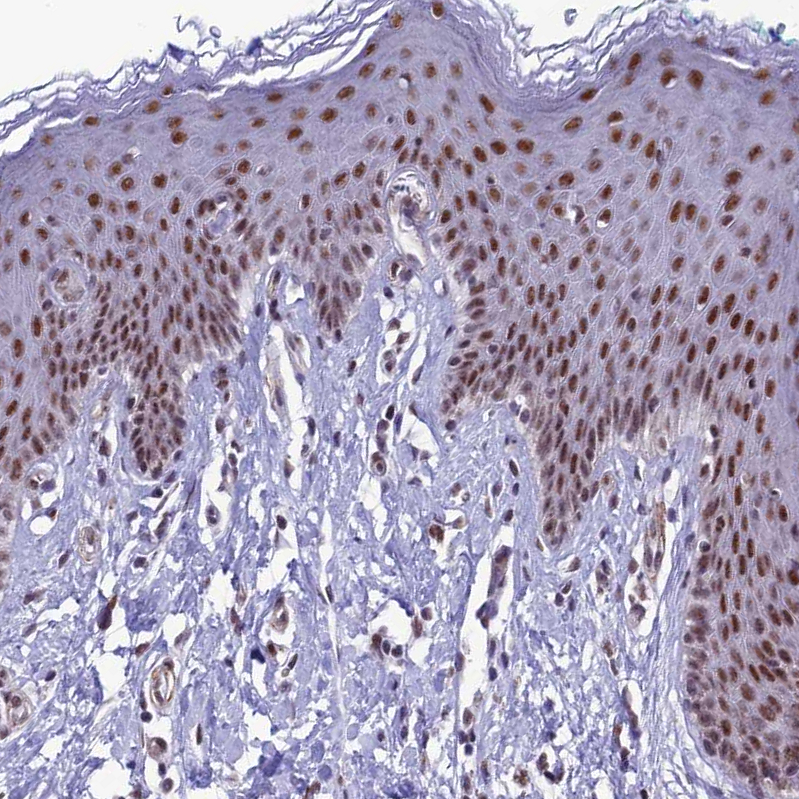

Immunohistochemical staining of human skin shows strong nuclear positivity in squamous epithelial cells.